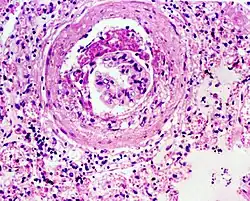

Glomerulosclerosis is the hardening of the glomeruli in the kidney. It is a general term to describe scarring of the kidneys' tiny blood vessels, the glomeruli, the functional units in the kidney that filter urea from the blood.

Proteinuria (large amounts of protein in the urine) is one of the signs of glomerulosclerosis. Scarring disturbs the filtering process of the kidneys and allows protein to leak from the blood into the urine. However, glomerulosclerosis is one of many causes of proteinuria. A kidney biopsy (the removal of a tiny part of the kidney with a needle) may be necessary to determine whether a patient has glomerulosclerosis or another kidney problem. About 15 percent of people with proteinuria turn out to have glomerulosclerosis.